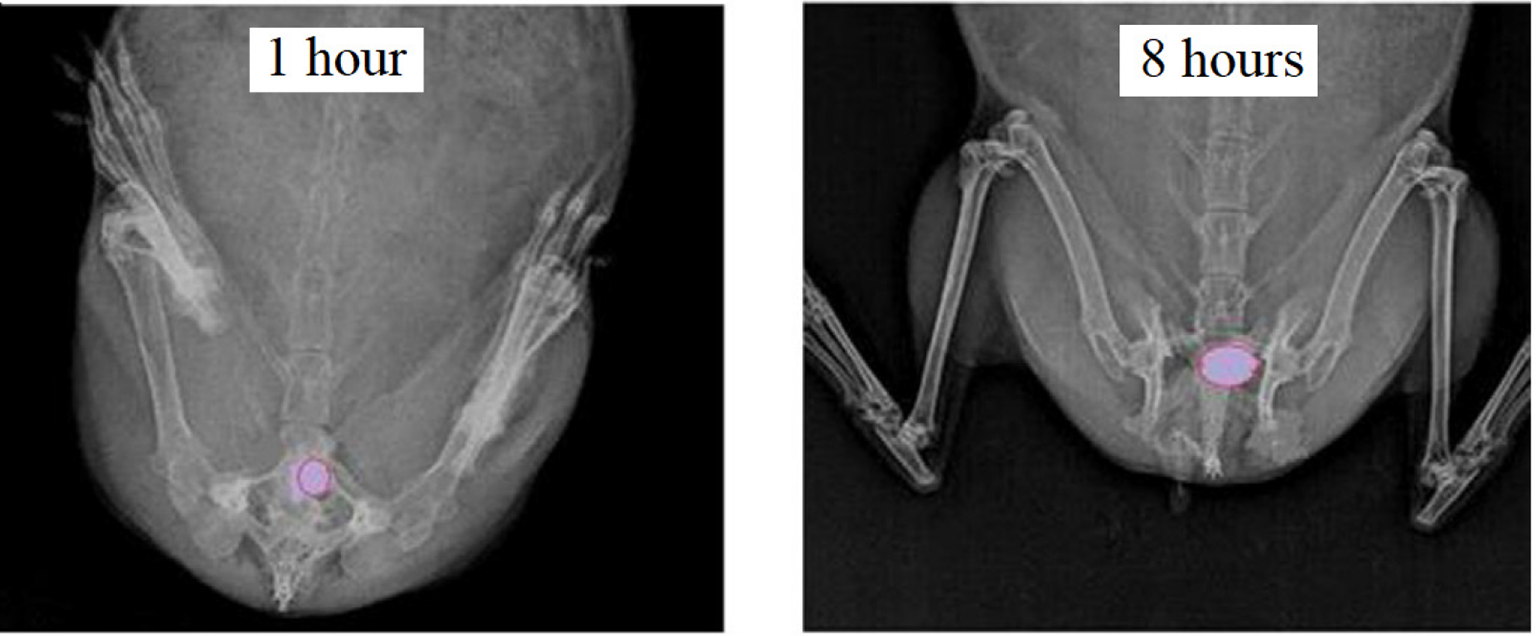

In this study, a new simple technique mimicking the vaginal environment was developed to investigate the release behavior of the vaginal tablet formulation. The apparatus mainly consists of a perfusor and syringe which are connected with a thin latex connector and a sample collection vessel as illustrated in Figure 6. (Pictures are reproduced from (36) and have received copyrights permission by the publisher on April 28, 2022.) The syringe used (without needle) has an internal diameter of 20 mm and total length of 75 mm to simulate the vaginal physiology. Tablets were placed at the bottom of the syringe and the assembly was dipped into a water at 37 ± 0.5°C. A perfusor was connected to the top of the syringe to supply a total of 6 mL of vaginal fluid to the tablets in 24 hours. The same amount of sample was collected concurrently from the bottom (36).